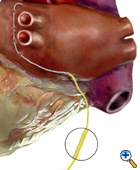

Left Atrial Cardioversion Wire

Figure 1. |

Arrested Heart Placement

The left atrial cardioversion wire (yellow) is the first wire to be implanted on the heart. It is placed before the valve repair/replacement or after the distal circumflex grafting is performed. The heart is lifted in order to have adequate exposure of the left pulmonary veins. The wire is attached to the left atrium anterior to and within 5mm of the left superior pulmonary vein. The wire is placed in a linear fashion with 2-4 bites of the atrial epicardium. The needle from the wire is cut and small crimp is made in the distal end of the wire. The wire is then draped over the dome of the left atrium or atrial appendage. This will allow 3 to 5 cm of wire to contact the epicardium. The wire is then brought out through the right side of the chest and secured to the skin with suture. A cardioversion connector is attached to the wire.